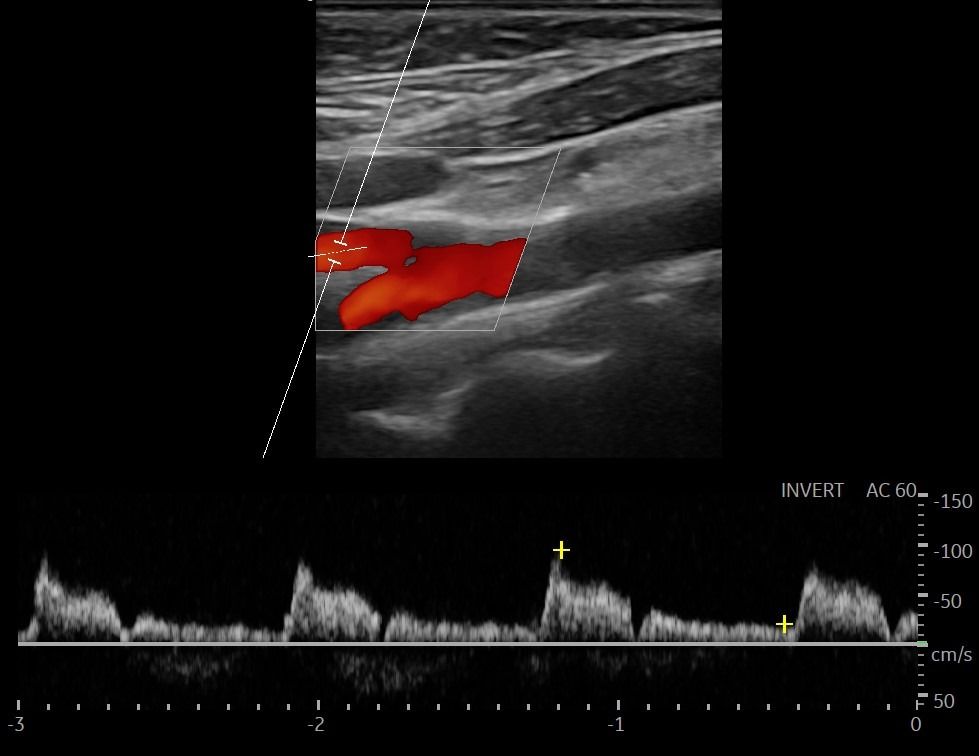

- Στένωση Καρωτιδικών Αγγείων: Η στένωση των καρωτιδικών αρτηριών μπορεί να αυξήσει την πιθανότητα εγκεφαλικού επεισοδίου. Το Triplex βοηθάει στη μέτρηση του ποσοστού στένωσης, επιτρέποντας την αξιολόγηση του κινδύνου.

- Αθηρωματικές Πλάκες: Η ποιότητα και η σταθερότητα των αθηρωματικών πλακών είναι κρίσιμη για την πρόβλεψη του κινδύνου αποκόλλησης και εμφάνισης εγκεφαλικού επεισοδίου. Η εξέταση εντοπίζει αν οι πλάκες είναι μαλακές και ασταθείς.

- Έγχρωμο Doppler: Αξιολογεί την ταχύτητα και την κατεύθυνση της ροής του αίματος, προσδιορίζοντας την ύπαρξη και το ποσοστό στένωσης των αρτηριών.

- Παλμικό Doppler: Παρέχει πληροφορίες για τις διακυμάνσεις της ροής του αίματος, βοηθώντας στην αναγνώριση πιθανών αιμοδυναμικών διαταραχών.